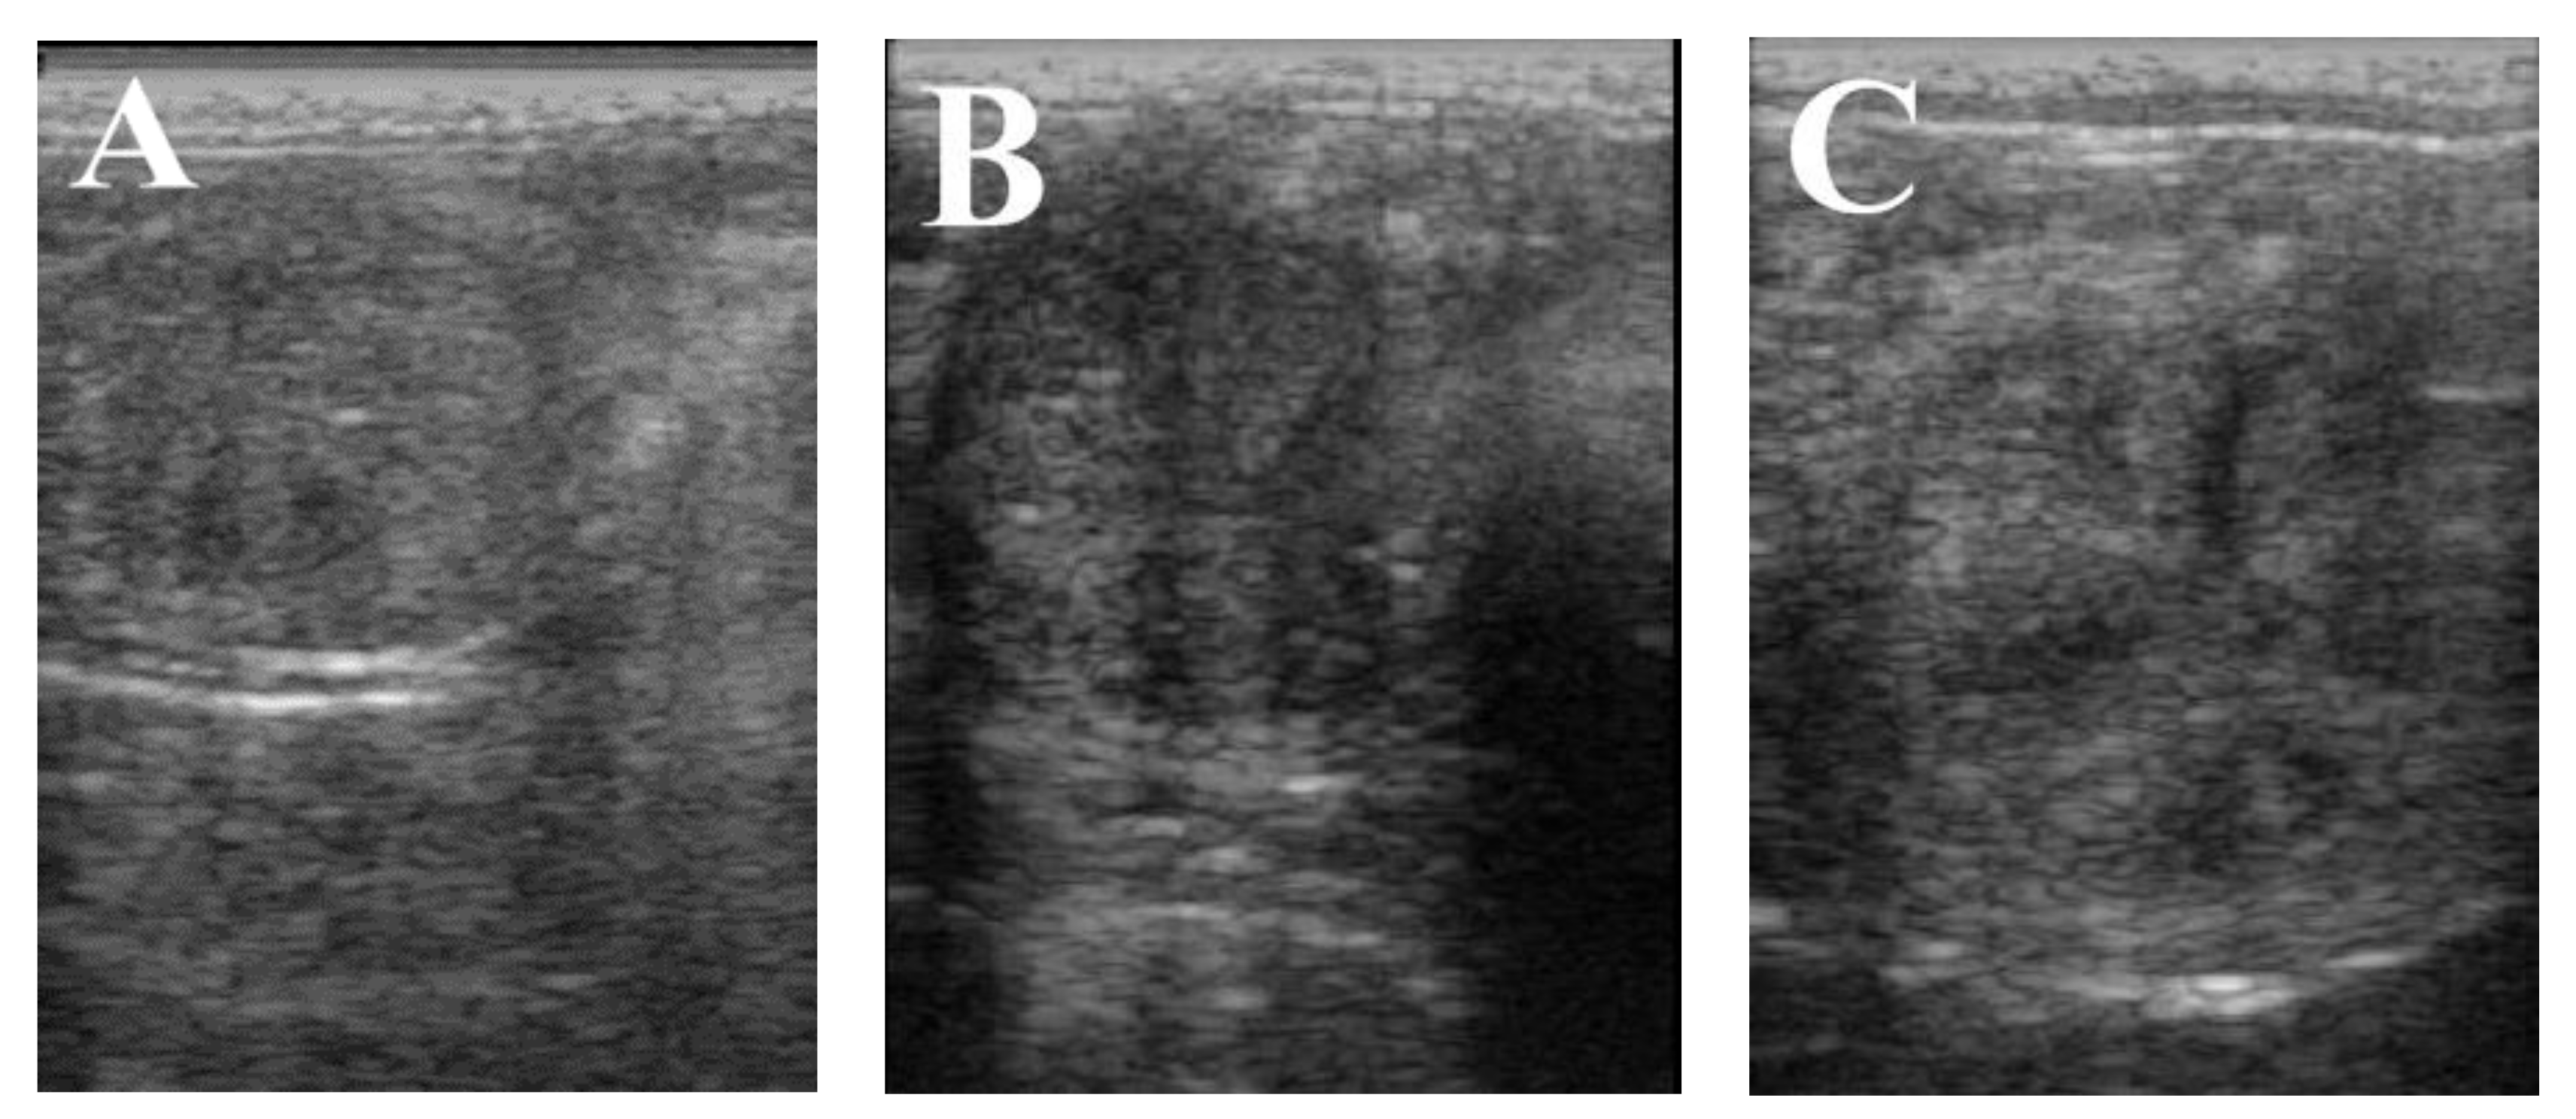

| Endometrium thickness (mm) | 5.87 c | 7.33 a | 6.86 b | 0.31 | 0.00 | Yes |

| Estrous cycle length (day) | 21.06 a | 9.63 b | 7.56 c | 0.05 | 0.00 | Yes |